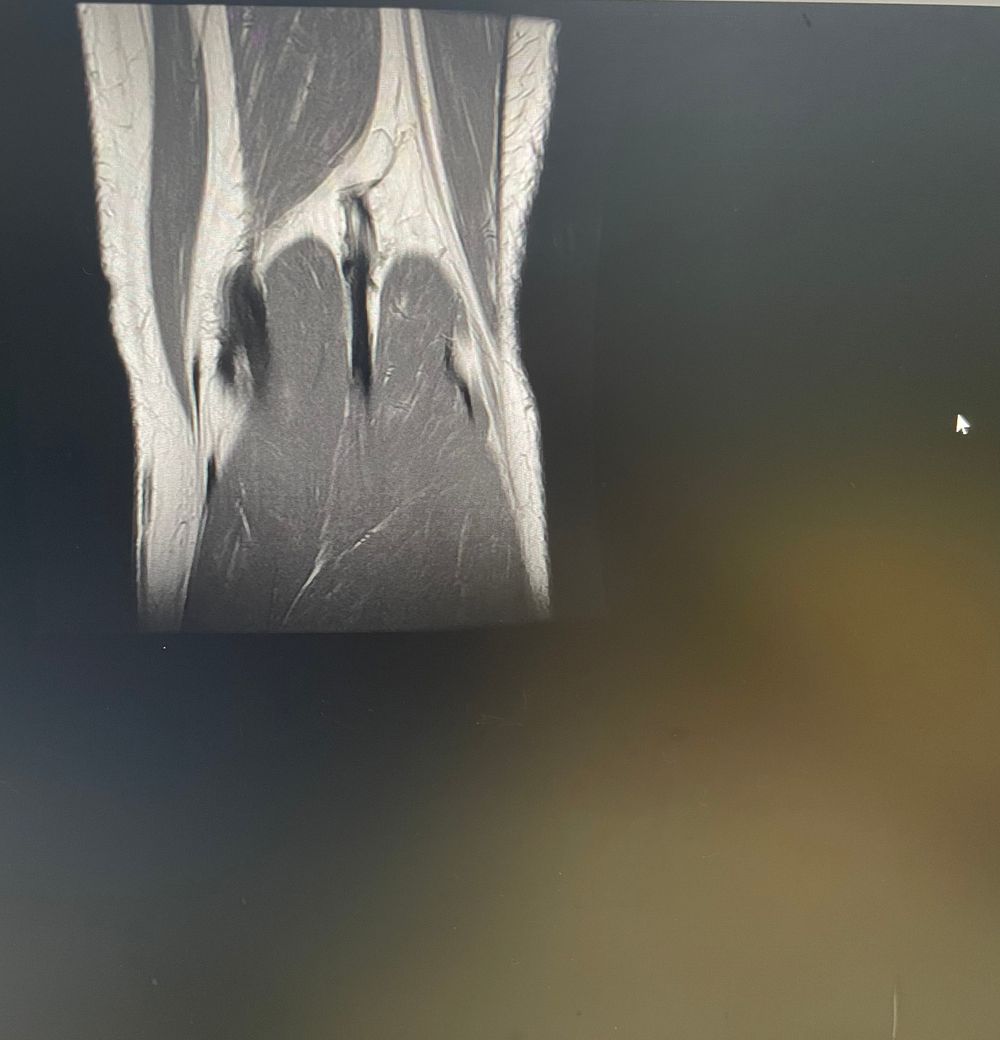

무릎 왼쪽 mri 사진 판독 부탁드리겠습니다.

안녕하세요 3달전쯤에 무릎을 다쳐서 약 한달전에 mri를 찍었습니다.

ACL 즉 전방 십자 인대에 불규칙한 소견은 있으나 Tear 즉 십자 인대가 파열되었다는

소견은 관찰되지 않는 상태이며 연골에 퇴행성 변화는 있는 것으로 보이나 이 역시 R/O

으로 확실하지 않음을 의미합니다. 결과적으로 십자 인대의 파열이 명확하지 않는 상태로

군대를 연기할 사유가 될지는 모르며 전방 십자 등 인대 손상의 경우는 명확하게 파열된

소견을 보이지 않는 경우, 군 입대에 문제가 되지는 않을 것으로 생각됩니다.